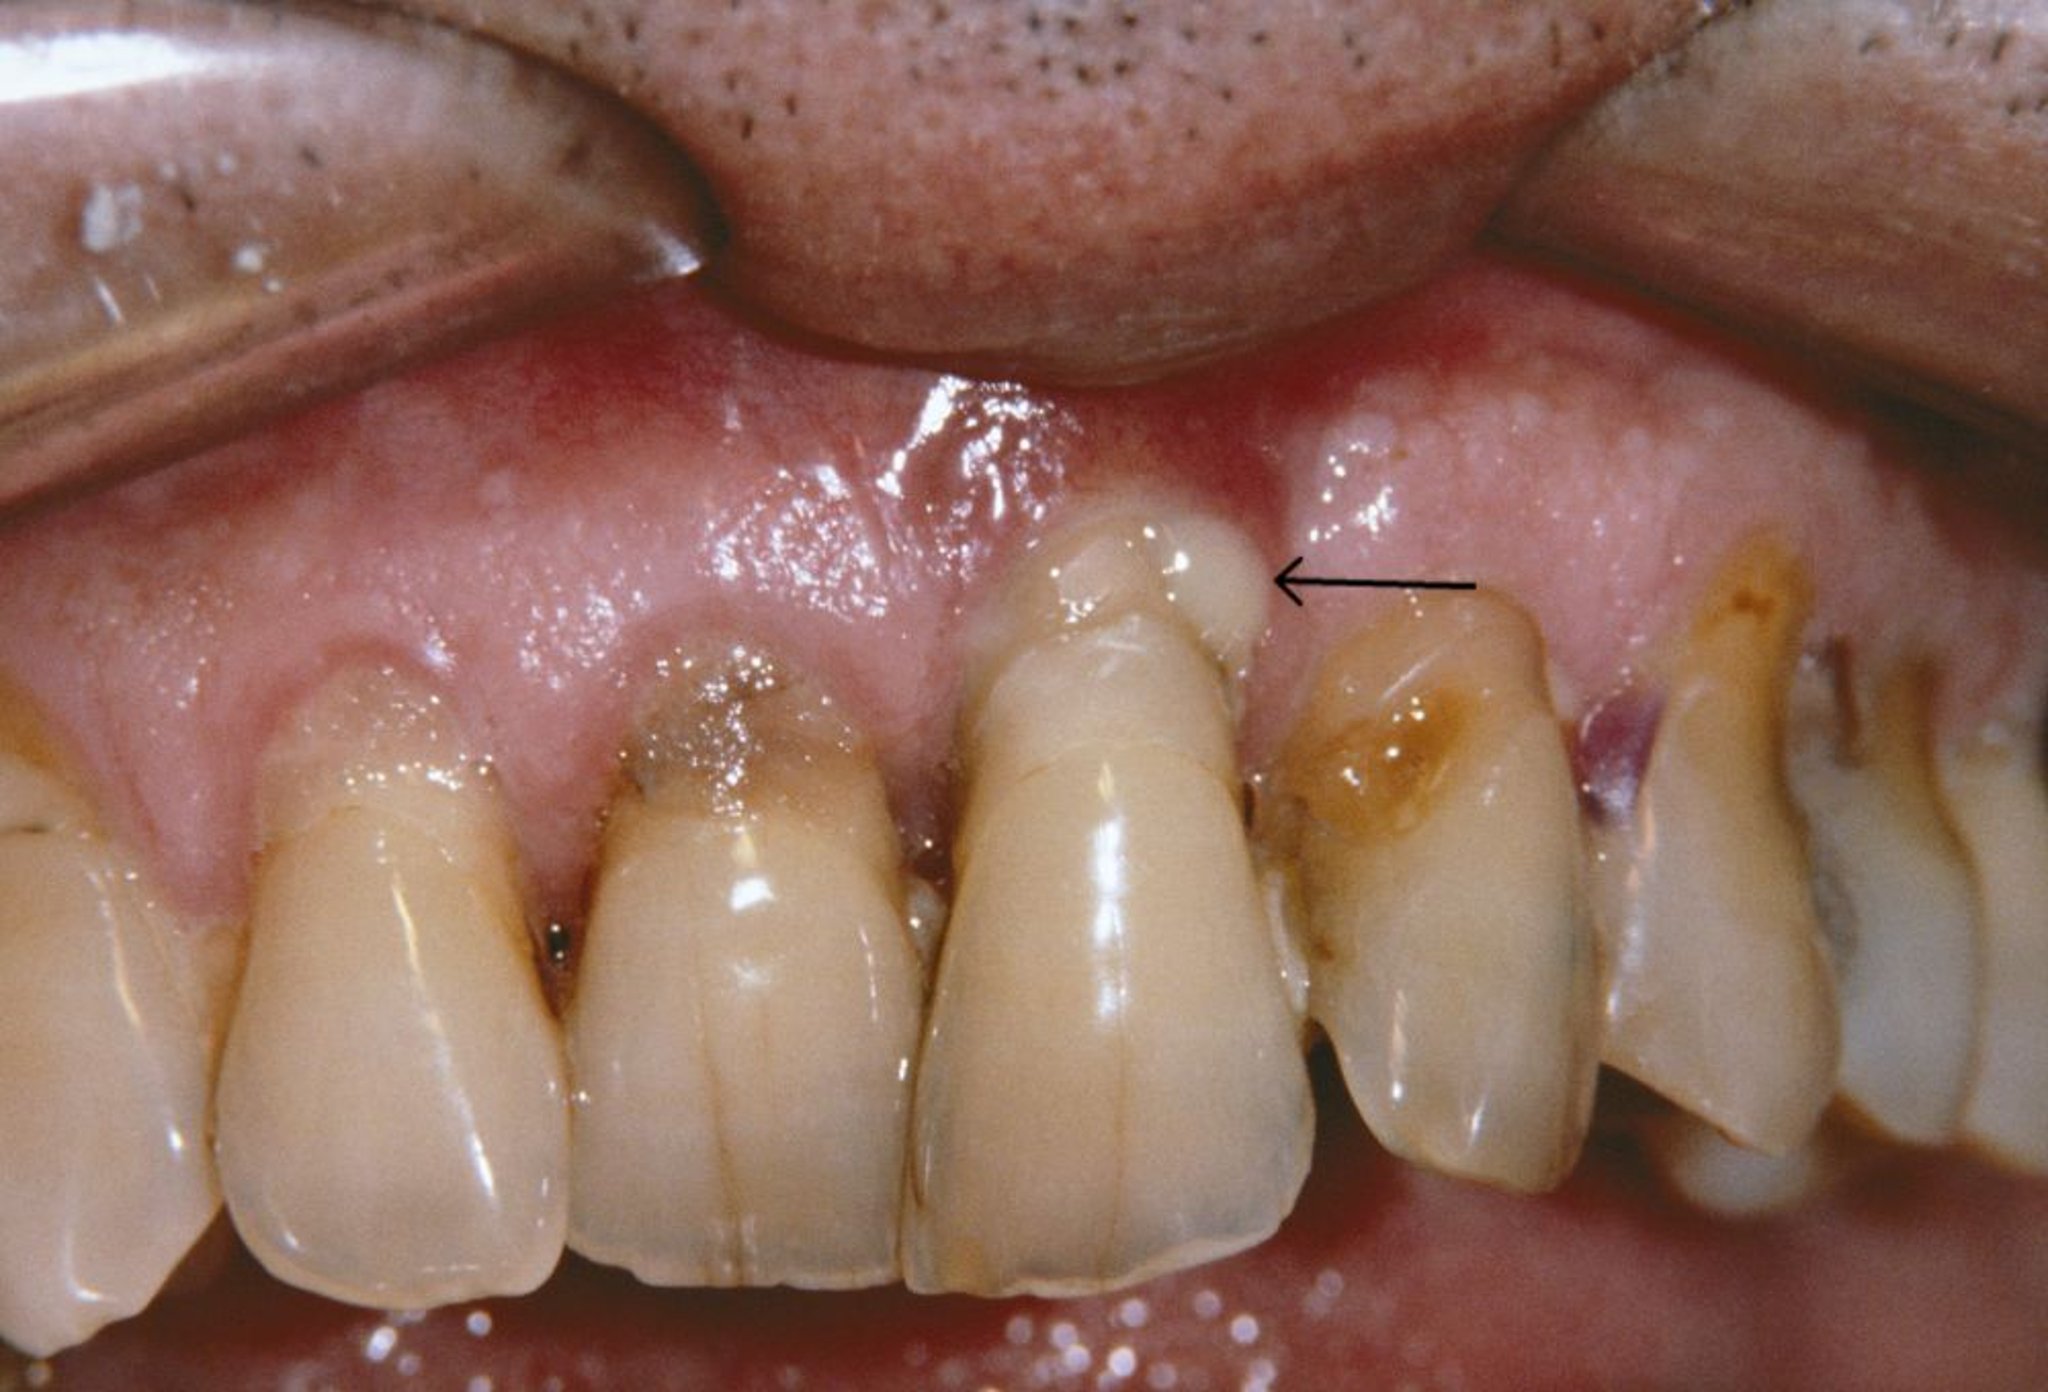

치주염

이 사진은 치주염이 있는 사람에서 퇴축 잇몸과 치주 농양(화살표)을 보여줍니다.

CNRI/SCIENCE PHOTO LIBRARY